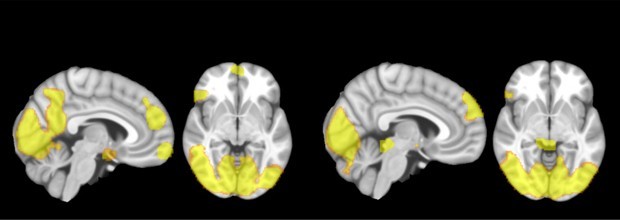

Disfunções em regiões específicas do cérebro resultam em atitudes incoerentes, não são doença, e portanto, cabíveis de punição; e não é desculpa para a ação. Comportamento agressivo também de influência genética, um gatilho disparado por causa de traumas na infância. Fatores ambientais ou disfunções do sistema límbico, devido a fatores emocionais, aumentam a probabilidade com a intensidade da ansiedade.

Fatores como culturais, educacionais e relação com a falta de conhecimento sugerem ações emocionais e incoerentes. Por mais que a pessoa tenha fatores que interferem nessas disfunções, através da plasticidade cerebral é possível balancear e aprimorar a conexão do córtex pré-frontal, região racional do cérebro com o sistema límbico, região do lobo temporal relacionado com o sistema emocional.

Outro detalhe que precisa ser observado é que o desequilíbrio entre os estímulos límbicos ascendentes e os mecanismos pré-frontais de controle descendentes resultam em comportamentos impulsivo-agressivos. A agressividade descontrolada pode ser causada pela baixa concentração de dopamina no cérebro, bem como outros neurotransmissores como a serotonina, a noradrenalina, entre outros, que afetam o equilíbrio entre os impulsos ascendentes e o controle descendente resultantes de estimulação aversiva ou provocativa.